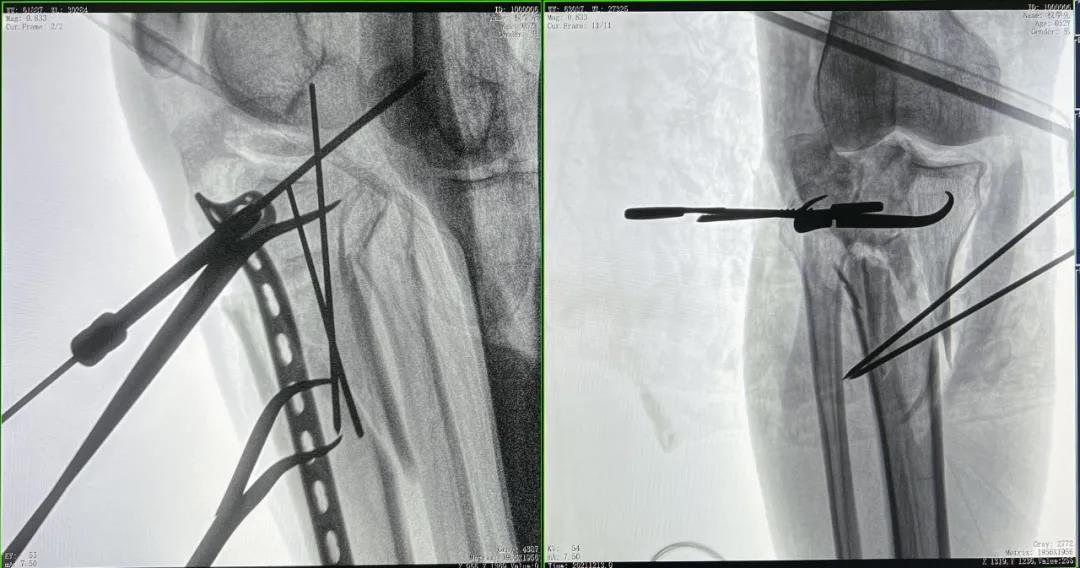

患者2:男性,52岁,胫骨骨折切开复位钢板内固定术

术前CT三维重建影像可见胫骨平台处粉碎性骨折

优质的术中影像辅助螺钉准确植入